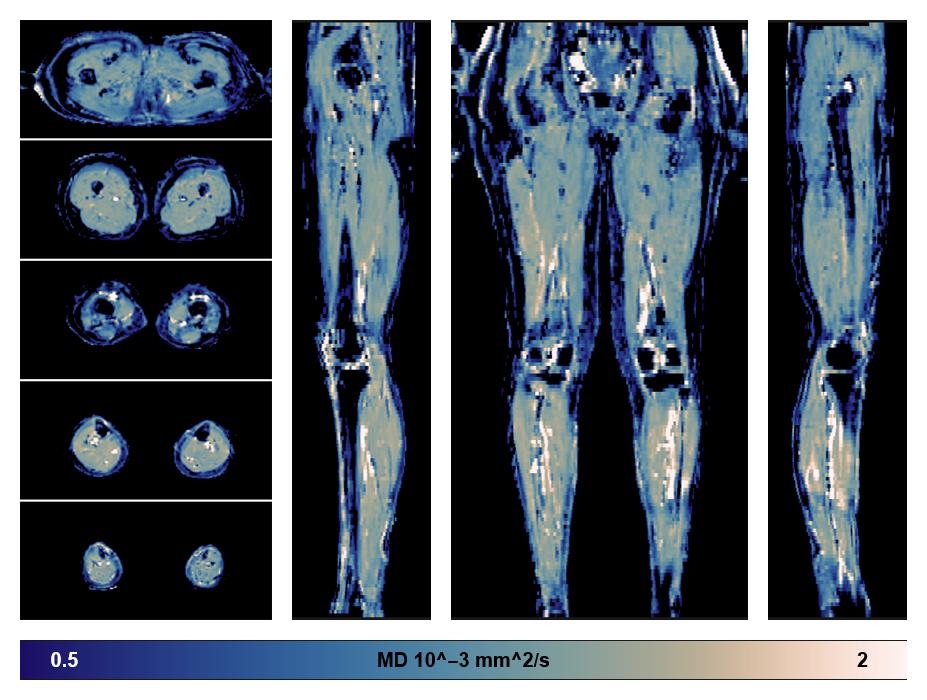

• Mean diffusivity

IVIM corrected whole leg muscle mean diffusivity obtained from diffusion tensor imaging.